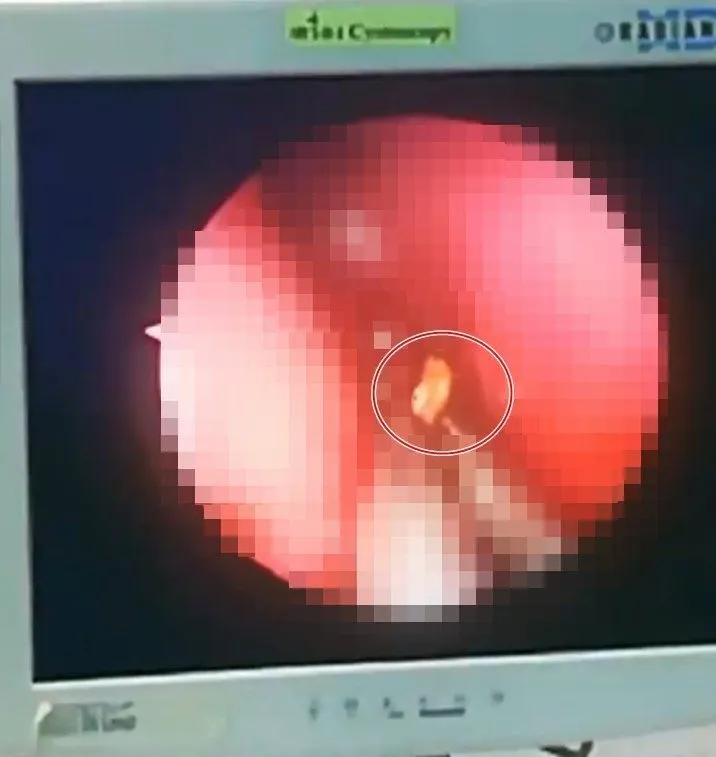

"#เศษไม้กว่า40ชิ้นในโพรงจมูก เมื่อสัปดาห์ที่แล้ว ผู้ป่วยชายอายุ46ปี ญาติพบว่าเมื่อเข้าใกล้จะมีกลิ่นเหม็นเน่า ลมหายใจกลิ่นแรงมาประมาณ1เดือน คิดว่าเป็นโรคภูมิแพ้ หรือไซนัสอักเสบ จึงตัดสินใจพามาโรงพยาบาล แพทย์เวรตรวจพบว่าในจมูกมีหนองไหลจึงส่งปรึกษาหมอหู คอ จมูก ส่องกล้องเข้าไปดูพบมีไม้เสียบในรูจมูก จึงเซ็ทเข้าห้องผ่าตัดเพื่อดมยาสลบ สิ่งที่เอาออกมาน่าตกใจมากครับ มีเศษไม้สั้นบ้างยาวบ้าง กว่า40ชิ้น มันเข้าไปอยู่ได้อย่างไร?"